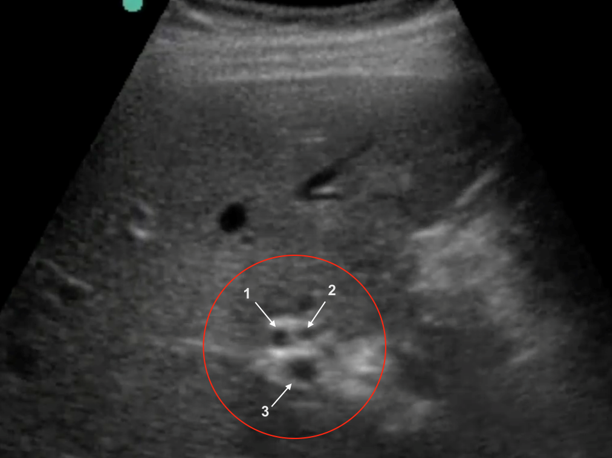

Gallbladder Common Bile Duct (CBD) – Transverse Image

1. Common Bile Duct (CBD)

2. Hepatic Artery

3. Portal Vein